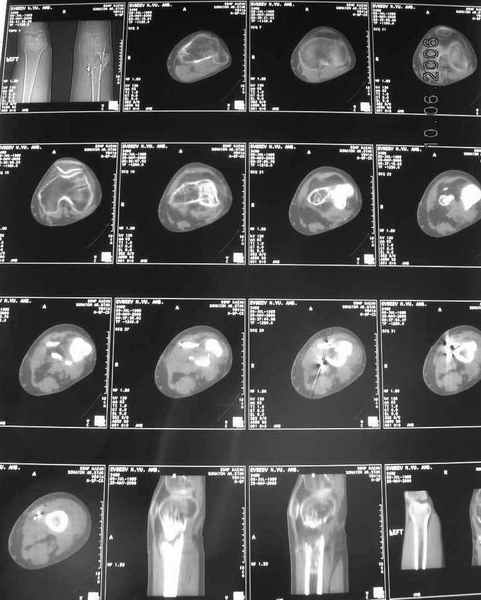

Рефрактур уж точно можно будет не опасаться, а за несколько месяцев даже при отсутствии заполнения костью по всей окружности, этот обходной "мостик" упрочнится и возьмет на себя нагрузку. В приложении пример такого рода "эндопротезирования диафиза", прошло больше 3 лет.

Пациентка, страдающая еще и инсулинозависимым диабетом, не хромает, работает инженером.